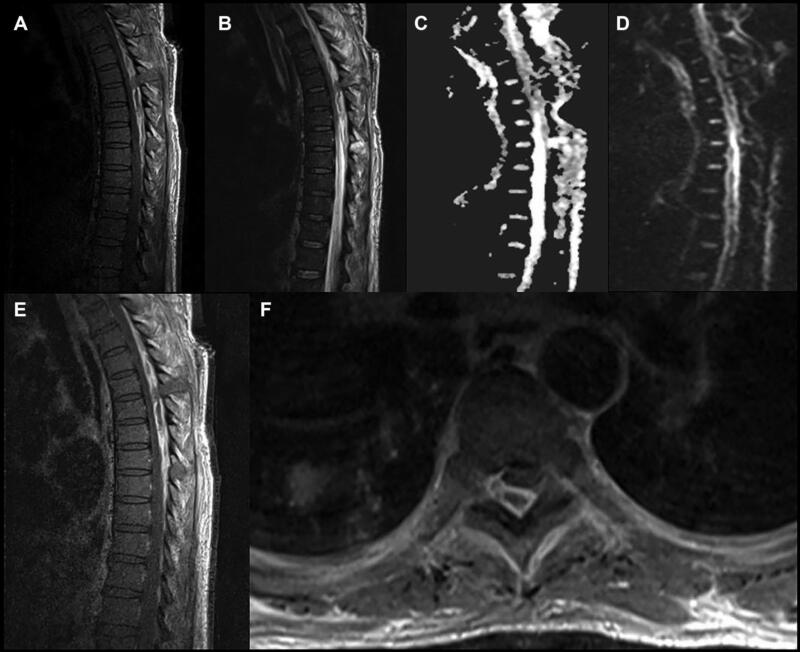

BN điều trị nội khoa thất bại hoặc có dấu hiệu chèn ép thần kinh, có thể cần phải chỉ định phẫu thuật (hình 1). Phẫu thuật nhằm cắt bản sống để giải ép các cấu trúc thần kinh, loại bỏ mô nhiễm khuẩn, và lây mô nuôi cấy định danh chủng gây bệnh. Nếu cột sống mất vững, có thể cần phải tiến hành làm cứng cột sống bằng xương ghép và đôi khi có bắt phương tiện kim loại. Xương ghép tự thân (autograft) được ưa thích hơn xương ghép đồng loại (allograft) vì giảm nguy cơ nhiễm trùng so với xương ghép đồng loại. Mặc dù một số phẫu thuật viên không dùng kim loại để làm cứng cột sống, nhưng nếu cần dùng thì nên sử dụng titanium hơn là thép không gỉ (stainless steel) vì titanium giảm nguy cơ nhiễm trùng (khả năng bám dính và tạo màng sinh học của vi khuẩn lên titanium kém hơn lên thép không gỉ). Trong một số trường hợp, để giảm nguy cơ nhiễm trùng, phẫu thuật làm cứng (fusion) cột sống có thể được thực hiện sau khi giải ép một thời gian, tức là mổ giải ép trước, điều trị kháng sinh, sau khi nhiễm trùng đã ổn định và được kiểm soát thì mổ làm cứng cột sống; hoặc có phẫu thuật viên mổ tháo phương tiện sau khi chụp phim kiểm tra thấy đã liền xương tốt.

Hình 1. MRI cột sống ngực có tiêm Gadolinium cho thấy khối áp xe ngoài màng cứng lan rộng ở nhiều đốt sống ngực. Hình A: Tổn thương tăng tín hiệu trên T1 (giảm tín hiệu trên T1 là hình ảnh điển hình của ap-xe ngoài màng cứng; tuy nhiên BN này có máu hiện diện trong tổn thương nên tạo ra hình ảnh tăng tín hiệu). Hình B: tăng tín hiệu trên T2, cho thấy khuếch tán giới hạn trên chuỗi xung Apparent diffusion coefficient (ADC) ở hình C và D (chuỗi xung DWI). Hình E: tổn thương bắt thuốc Gado, tăng tín hiệu trên T1 có tiêm Gado. Trên phim axial ở hình F, hình ảnh bắt thuốc của khối ap-xe đẩy túi màng cứng ra trước. BN này ban đầu có biểu hiện nhiễm trùng do catheter chạy thận nhân tạo bị nhiễm khuẩn. Sau đó phát hiện apxe ngoài màng cứng ở cột sống ngực, BN được phẫu thuật can thiệp tối thiểu cắt nửa bản sống (minimally invasive hemilaminectomies) để dẫn lưu mủ nhưng thất bại, sau đó đã được mổ cắt bản sống T2-T8.